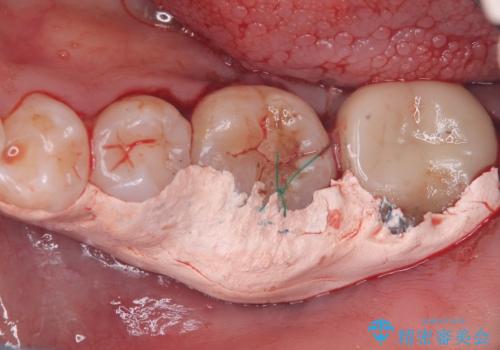

保存が難しい左下6番目の歯を抜歯し、左下8番目の歯(親知らず)を抜歯窩に移植しました。歯牙移植後の動揺防止のため暫間固定を行っています。

また移植後2週間経過時点で根管処置が必要となります。